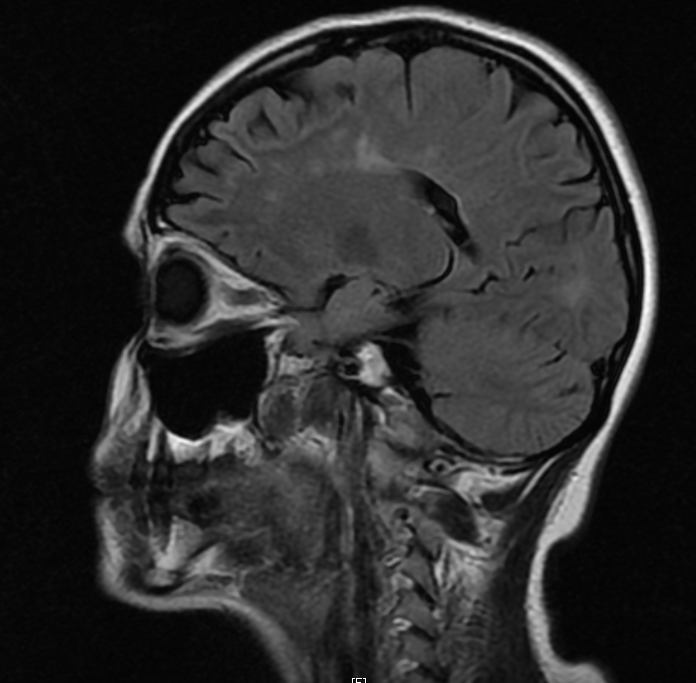

Objetivo: Relatar o caso de recidiva de herpes-zoster (HZ) em paciente com esclerose múltipla (EM) em uso de tratamento imunomodulador (natalizumabe) com evolução favorável. Descrição de caso: Mulher de 39 anos com diagnóstico de EM há 1 ano e 6 meses, previamente tratada com interferon 1a, começou tratamento com natalizumabe, desenvolvendo HZ após três meses de tratamento. HZ foi tratado com aciclovir, por sete dias, via oral. Seguimento ambulatorial após três meses de tratamento mostrou resolução completa das lesões, sem desencadeamento de neuralgia pós-herpética. Conclusões: As novas terapias para a EM podem estar relacionadas a diferentes tipos de efeitos adversos. Nem todos os casos de HZ, associados com novas terapias para EM, evoluem de forma desfavorável. Estudos são necessários para reconhecer os fatores de riscos para as formas graves de HZ em tais pacientes.